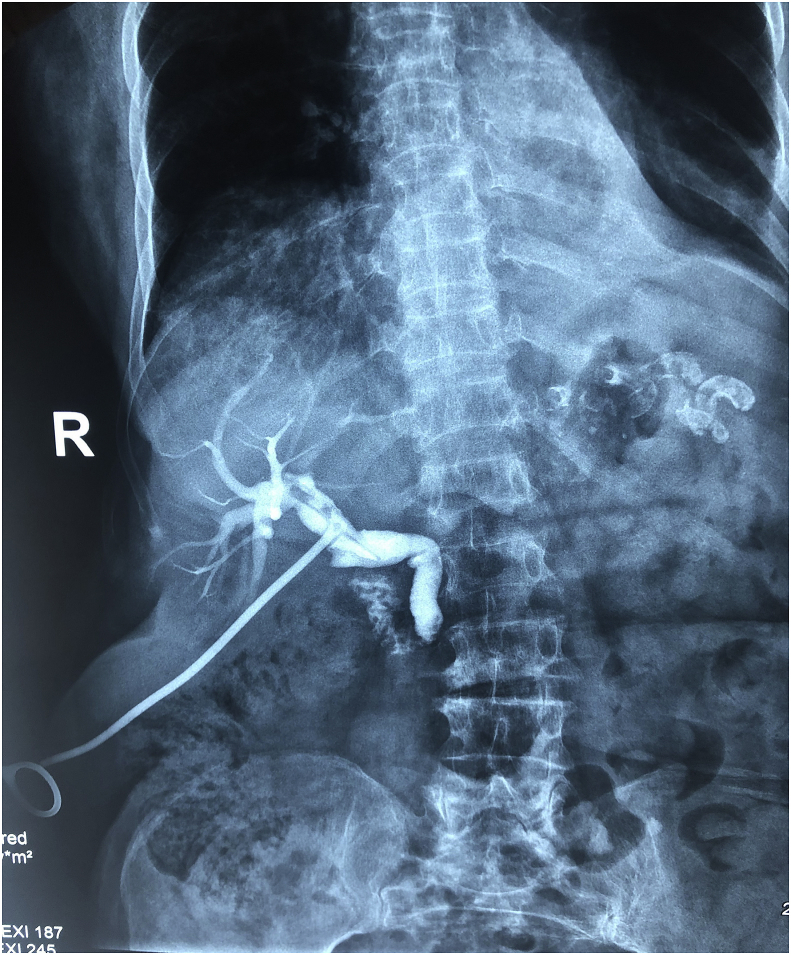

Follow-up and outcome: The patient was admitted to the hospital for 1 week, at the 14th day T-tube cholangiography was done which showed the passage of the dye to the duodenal lumen with no residual stones, the T-tube was extracted and the patient was discharged home with no postoperative complications. Fig. 4.